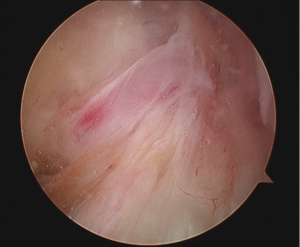

Arthroscopy revealed that the large ACL ganglion cyst was both intra-substance and extending in the posterior direction (Figures 2,3). A posteromedial portal was created to assist in visualising the ganglion from the back of the knee and to allow complete excision. The content consisted of a yellowish gelatinous material (Figure 4).